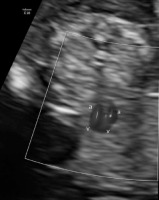

Moreover, the fetal heart seemed to possess four cavities, two slightly asymmetrical inflows of the ventricles and the origins of two vessels in abnormal relationships were visualized (Figures 4-5).